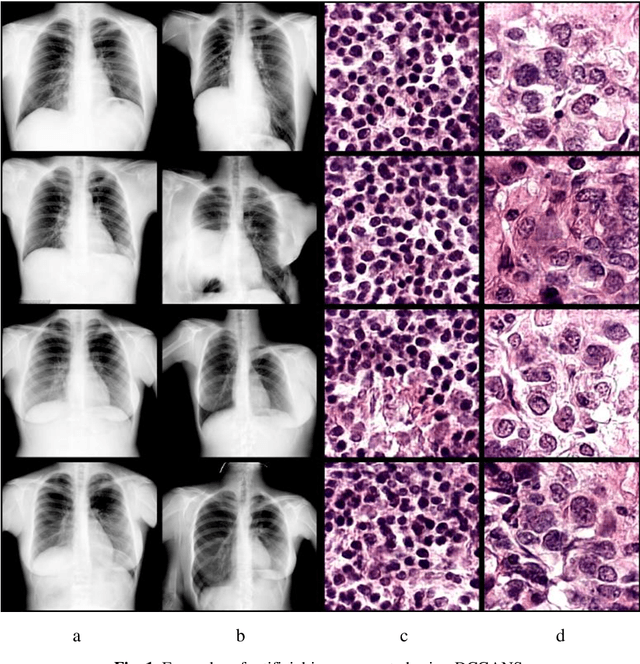

Abstract:In this paper, we explore the possibility of generating artificial biomedical images that can be used as a substitute for real image datasets in applied machine learning tasks. We are focusing on generation of realistic chest X-ray images as well as on the lymph node histology images using the two recent GAN architectures including DCGAN and PGGAN. The possibility of the use of artificial images instead of real ones for training machine learning models was examined by benchmark classification tasks being solved using conventional and deep learning methods. In particular, a comparison was made by replacing real images with synthetic ones at the model training stage and comparing the prediction results with the ones obtained while training on the real image data. It was found that the drop of classification accuracy caused by such training data substitution ranged between 2.2% and 3.5% for deep learning models and between 5.5% and 13.25% for conventional methods such as LBP + Random Forests.